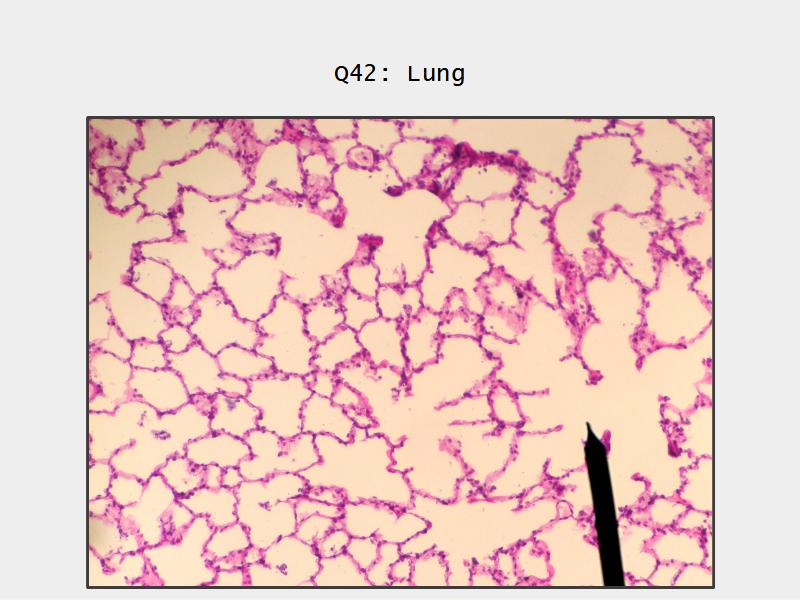

- Slide 72 & 74: Lung

Lungs